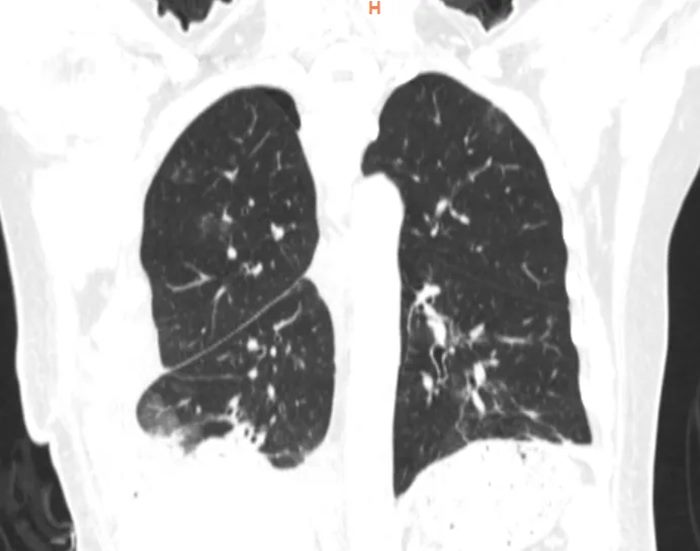

检查发现,马女士右侧胸腔及纵隔内见巨大团片状低密度影,累及左侧胸腔致心脏大血管及气管向左侧胸腔偏移,以脂肪密度为主。肿瘤累及气管、左右主支气管、上腔静脉及主动脉外膜、部分心包、左右下肺静脉,累及并包埋食管及下腔静脉,右肺受压不张。而接下来的手术堪称一场惊心动魄的生命之战。

经过胸外科高兴才主任团队、麻醉科胡强夫主任团队等科室充分准备,输血科魏明主任团队积极备血后,手术按计划如期进行,选择右胸第6肋后外侧切口进胸,因肿瘤体积巨大,占满胸腔,纵隔移位,累及上纵隔、中纵隔、后纵隔,并包绕主动脉及上、下腔静脉、食管。手术空间狭窄,视野受限,术中联合胸腔镜辅助手术,行胸腔及纵隔巨大肿瘤满意切除、心包部分切除。